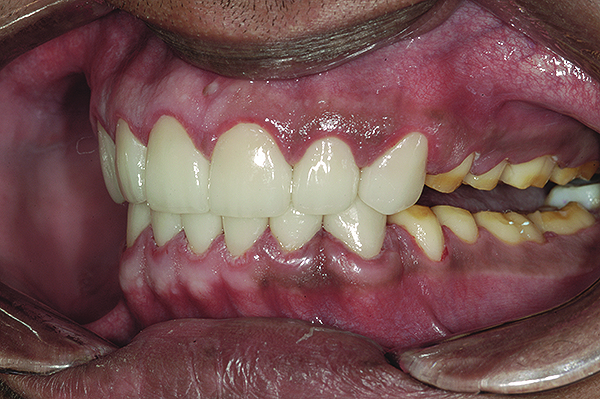

Figure 16. Anterior final restorations bonded.

Figure 16

The anterior restorations were fabricated with low-translucency lithium-disilicate ingots and layered in the incisal half to provide the desired internal characteristics in accordance with the patient’s age. The final anterior restorations were then tried-in and verified for marginal fit, esthetics, and phonetics. After the patient’s approval, they were bonded using dual-cured resin cement (Variolink® II, Ivoclar Vivadent) (Figure 16). Because the enamel in such cases is already compromised, bonding can become clinically unpredictable. A self-etching primer was used on the teeth, followed by a bonding agent (Clearfil™ ST Bond, Kuraray Dental, www.kuraraydental.com) that was light-cured for 20 seconds. The intaglio of the crowns was prepared by etching with 9% buffered hydrofluoric acid for 60 seconds and silanating them to achieve optimum bonds to the resin cement.18

The final restorations were fabricated in the laboratory using monolithic lithium disilicate, and then tried-in in the patient’s mouth and verified for esthetics and function. They were then bonded with dual-cured resin cements following the same protocol as outlined for the anterior teeth.

The final restorations depicted restoration of form, function, and beauty, with good harmony of restoration and the periodontium (Figure 19 through Figure 25). MIP was in harmony with CR, and right and left lateral excursion discluded all posteriors with anterior group function. The postoperative orthopantomogram (OPG) (Figure 26) shows the treatment done while maintaining the vitality of anterior teeth.